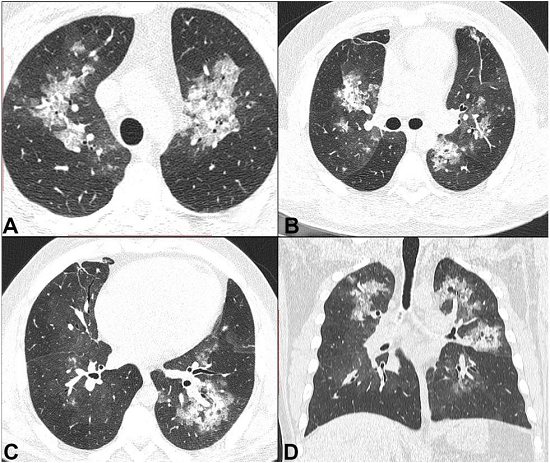

A 36-year-old mulatto male patient sought the emergency facility complaining of lumbar pain of progressive intensity over the past 3 days that worsened with trunk movement. This symptom irradiated to the dorsum and was accompanied by breathlessness. Concomitantly, he complained of wheezing, a cough with mucoid sputum, which was soon followed by dark urine. He had known diagnosis of SCD since the age of 23 years when he experienced an episode of priapism that required surgical intervention. Since then he had not followed any medical treatment. However, he experienced repeated episodes of bone pain, for which he used over-the-counter painkillers as self-medication. He ignored the same diagnosis among his relatives. He smoked for 2 years in his youth and still consumed alcoholic beverages. On physical examination, he was slightly pale, non-icteric and afebrile. His pulse rate was 124 beats per minute, blood pressure 110/80 mmHg, respiratory rate 28 respiratory movements per minute (rmpm), and room air oximetry was 83%. His body mass index was 25. No edema or lymphadenopathy were found. The heart and lungs examination was unremarkable; however, the abdomen was diffusely tender and the liver was palpable 2 cm below the right costal margin. The examination of his back and lumbar region was normal. The laboratory work-up disclosed normocytic normochromic anemia with a hemoglobin of 10.9 g/dL (reference value [RV]: 12.3-15.3 g/dL); hematocrit of 30.1% (RV: 36-45%); red cell distribution width of 20.6% (RV: 14%); leukocytosis with the presence of myelocytes and metamyelocytes in the peripheral blood; and a normal platelet count. The peripheral blood film revealed the presence of poikilocytosis, target cells, and stomatocytes; rare erythrocytes showed the presence of Howell-Jolly bodies, 20 polychromatic, 19 orthochromatic erythroblasts per 100 leukocytes and occasional sickled erythrocytes. Reticulocyte count was not available. C-reactive protein was 173 mg/L (RV: <5 mg/L), lactate dehydrogenase 686 U/L (RV: <250 U/L), and a total bilirubin 1.49 mg/dL (RV: <1.2 mg/dL) at the expense of indirect bilirubin. The renal function tests, electrolytes, liver enzymes, and urinalysis were normal. Blood and urine cultures were negative. The chest x-ray and computed tomography (CT) revealed peri-hilar bilateral confluent ground-glass opacities rendering small consolidations (Figures 1 and 2). An apparently calcified spleen of reduced dimension was an additional finding.

Chest radiography usually reveals unspecific diffuse or patchy bilateral opacities.23 In contrast, chest CT may be useful to evaluate the patients with the potential diagnosis of FES, and, more importantly, to rule out or demonstrate an alternative diagnosis. The most common finding on the CT is the patchy ground-glass opacities, which are usually associated with interlobular septal thickening (crazy-paving pattern), and eventually airspace consolidation and small centrilobular nodules.27

Our patient presented with abdominal and lumbar pain, hypoxemia, and bilateral lung opacities, and a history of sickle cell disease, which led to the diagnosis of vaso-occlusive crisis and acute chest syndrome (ACS). This clinical presentation fulfilled the criteria for ACS, since there was a new radiographic pulmonary infiltrate associated with hypoxemia, tachypnea, cough, and wheezing.33 Fat embolism is one of the proposed underlying mechanisms of ACS.34 Our patient had neither petechial rash nor central nervous system depression prior to his cardiac arrest. The diagnosis of FES was not made ante-mortem possibly because of the lack of its clinical hallmarks and its resemblance with ACS. The chest imaging also led to a diagnosis of a possible lung infection. Moreover, FES is a rare event in non-traumatic patients, whereas ACS is a frequent diagnosis in Brazilian emergency rooms.